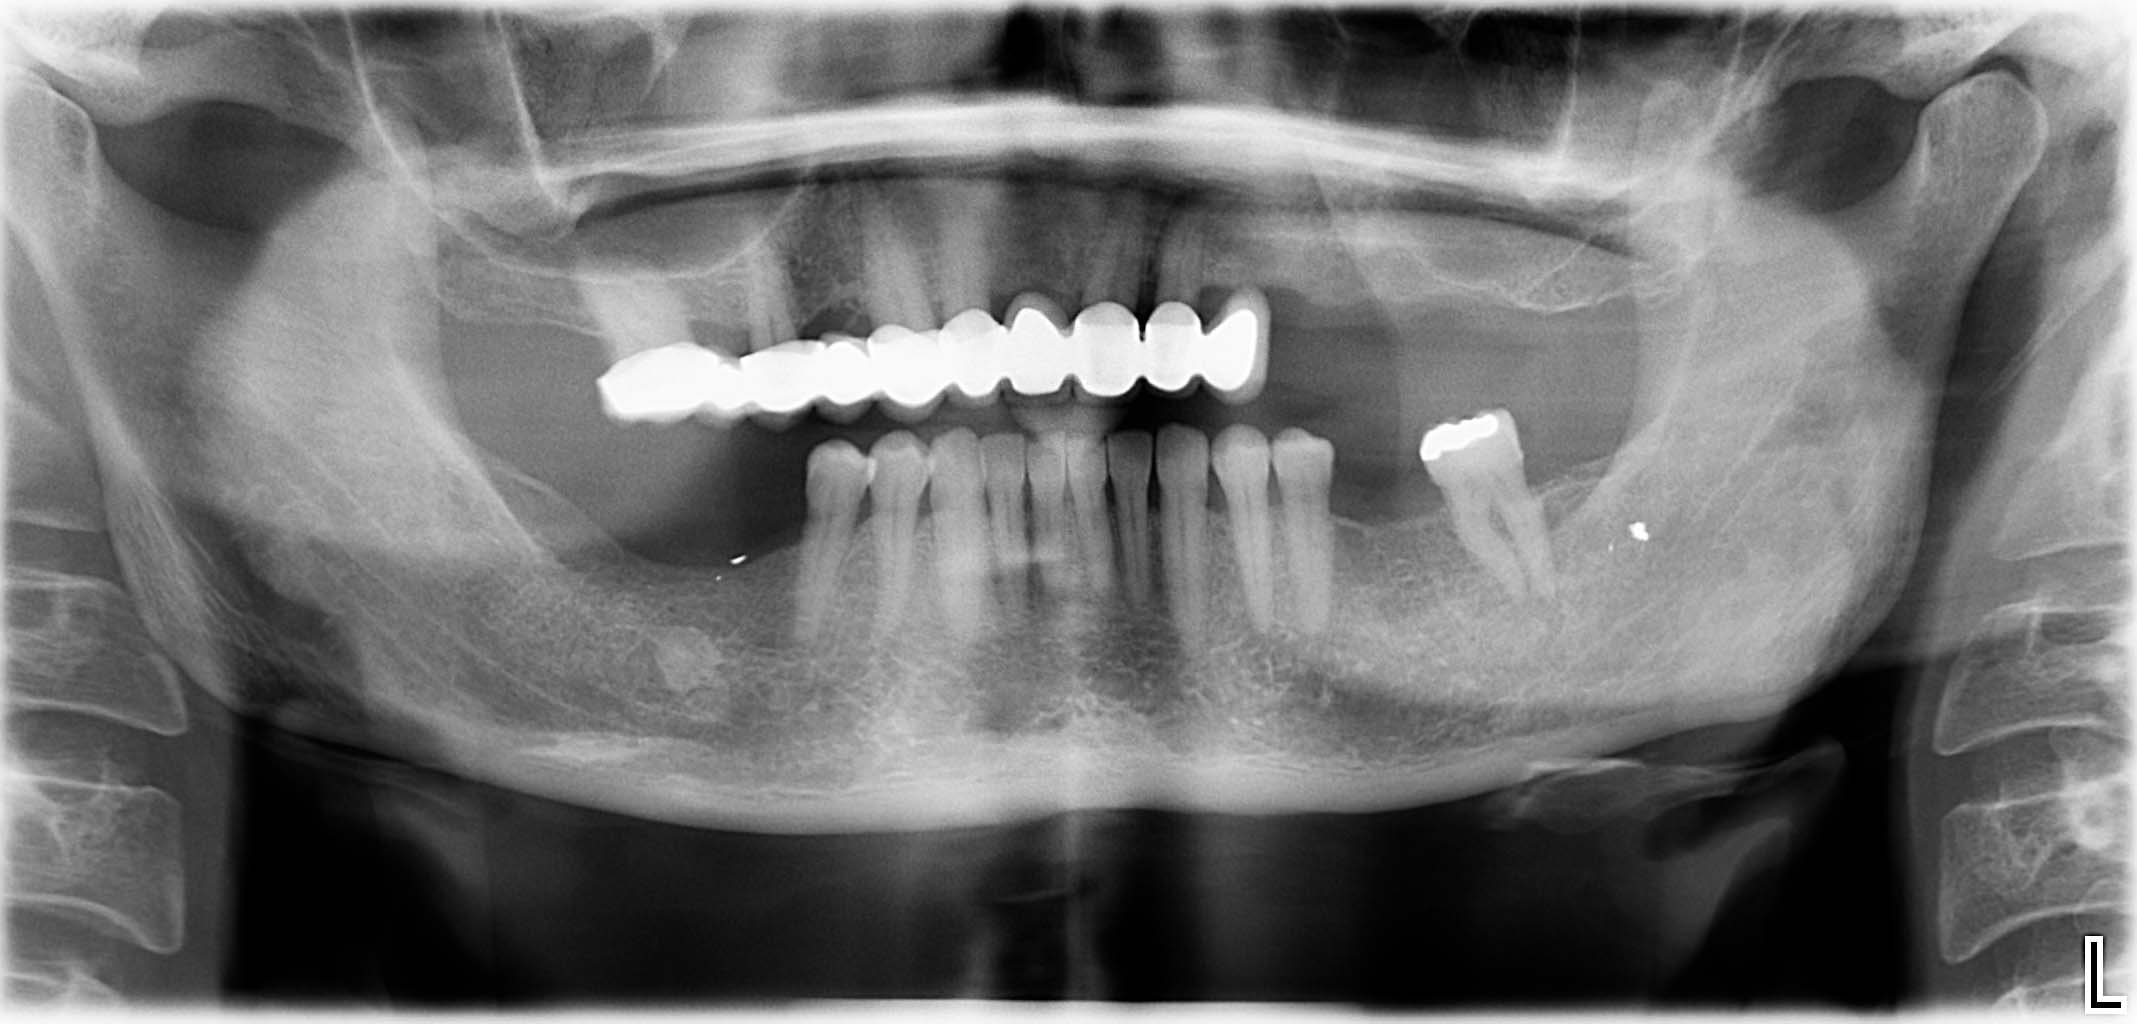

Ausgangssituation: Zahn 36 mit apikaler Beherdung, nicht erhaltungswürdig